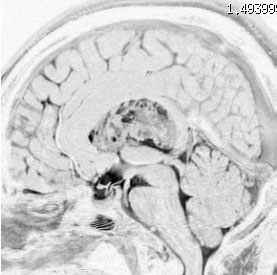

無症状で偶然発見された38歳女性の症例

central neurocytomaが透明中隔 septum pellucidum から発生していることがよくわかる症例です。症状はありませんでしたが,この腫瘍がこのままのサイズで留まることはあり得ないので手術摘出を勧めました。これ以上大きくなると手術にしても放射線治療にしてもリスクが大きくなりすぎます。脳弓にくっつくので脳弓損傷を避けるのが手術のポイントです。脳室壁にくっつくのですが剥がしていけば取れますが,大きな上衣下静脈 large subependymal vein の損傷には注意を払います。

手術後の画像です。脳神経外科の先生は手術根 surgical track に注目して下さい,左頭頂葉皮質切開 transcortical approachで手術を行っています。このルートでは全く手術後の神経脱落症状が出ませんでした。central neurocytomaの手術方法は,上記に加えて前頭葉皮質切開でまっすぐ前角に入る方法と経脳梁法 transcallosal approachがあります。経脳梁法は限られた小さめの腫瘍にしか応用できません。anterior callosal approach以外ではdisconnection syndromeが出るからです。central neurocytomaは脳室の壁にベトベトくっつくし,anterior callosal approachでは脳室壁の観察はかなり限られるからです。大きなものでは必ず経皮質法を選択して下さい。